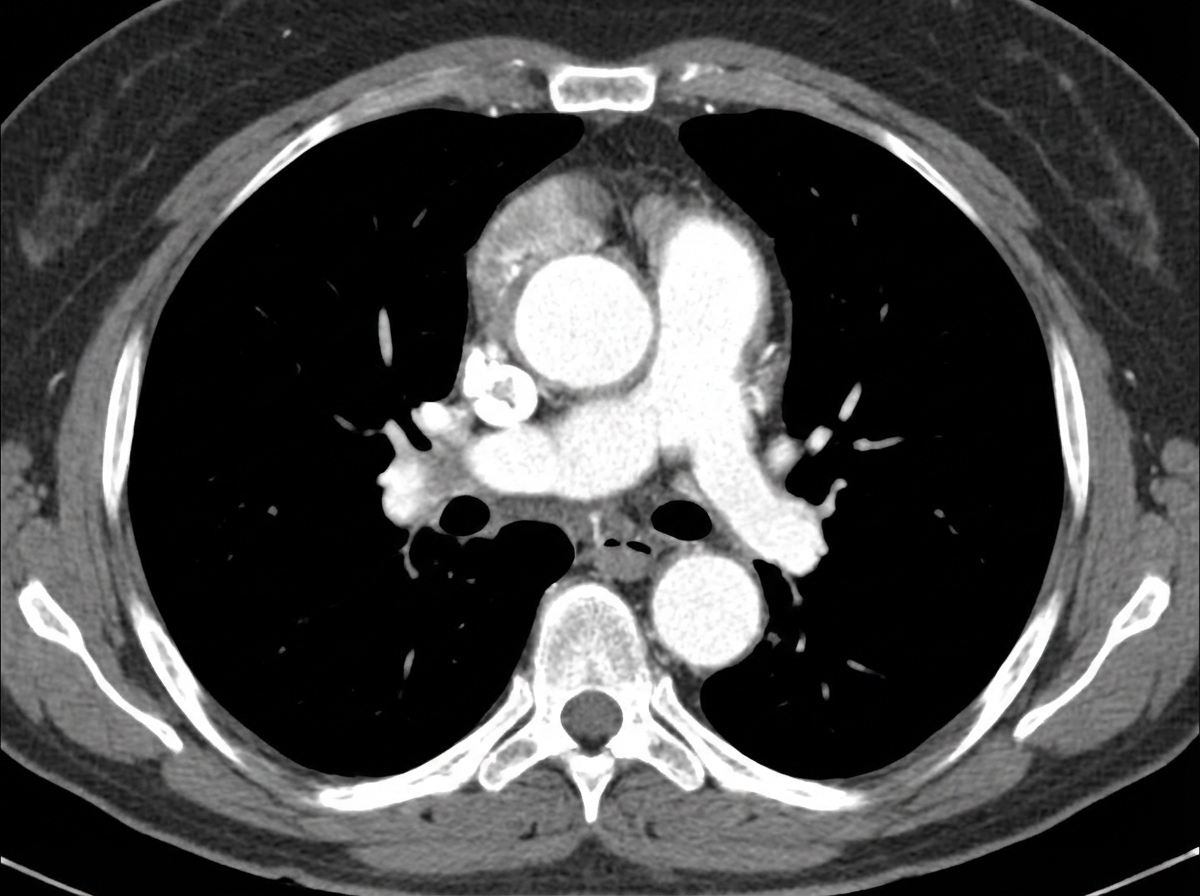

A 43-year-old man from Chile comes to the physician because of a 1-day history of upper back pain and difficulty swallowing. He has had pain in his shoulder and knee joints over the past 10 years. He is 190 cm (6 ft 3 in) tall and weighs 70.3 kg (155 lb); BMI is 19.4 kg/m2. His blood pressure is 142/86 mm Hg in the right arm and 130/70 mm Hg in the left arm. Physical examination shows a depression in the sternum and a grade 3/6 diastolic murmur at the right upper sternal border. A CT scan of the chest with contrast is shown. Which of the following is the most likely underlying cause of this patient's condition?